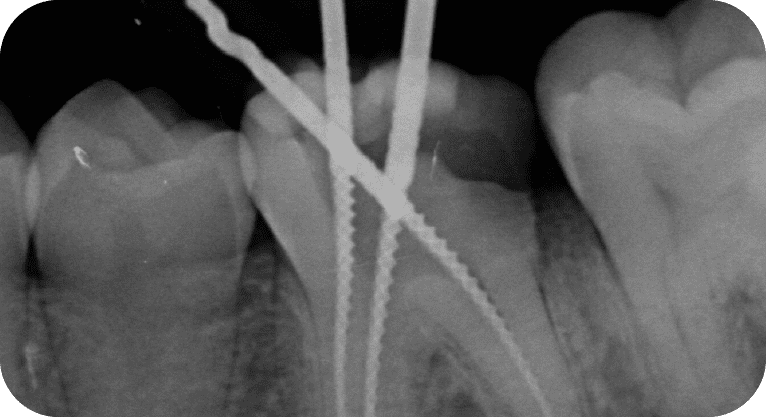

Male patient, “25” years old

Treatment: Root canal treatment

The patient had pain in two molars due to deep cavities. Root canals were performed on both teeth, disinfecting and sealing the canals, followed by zirconia crowns to restore their function.